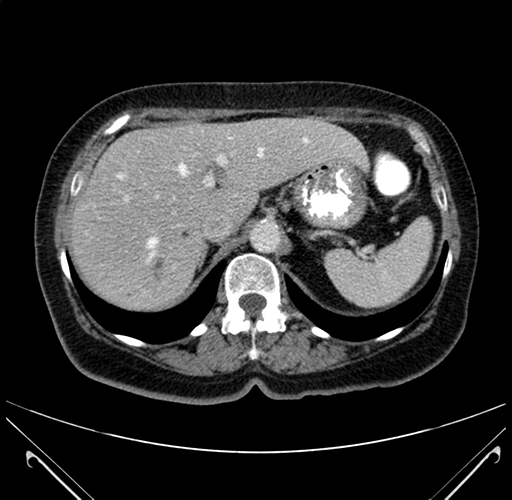

Axial Venous